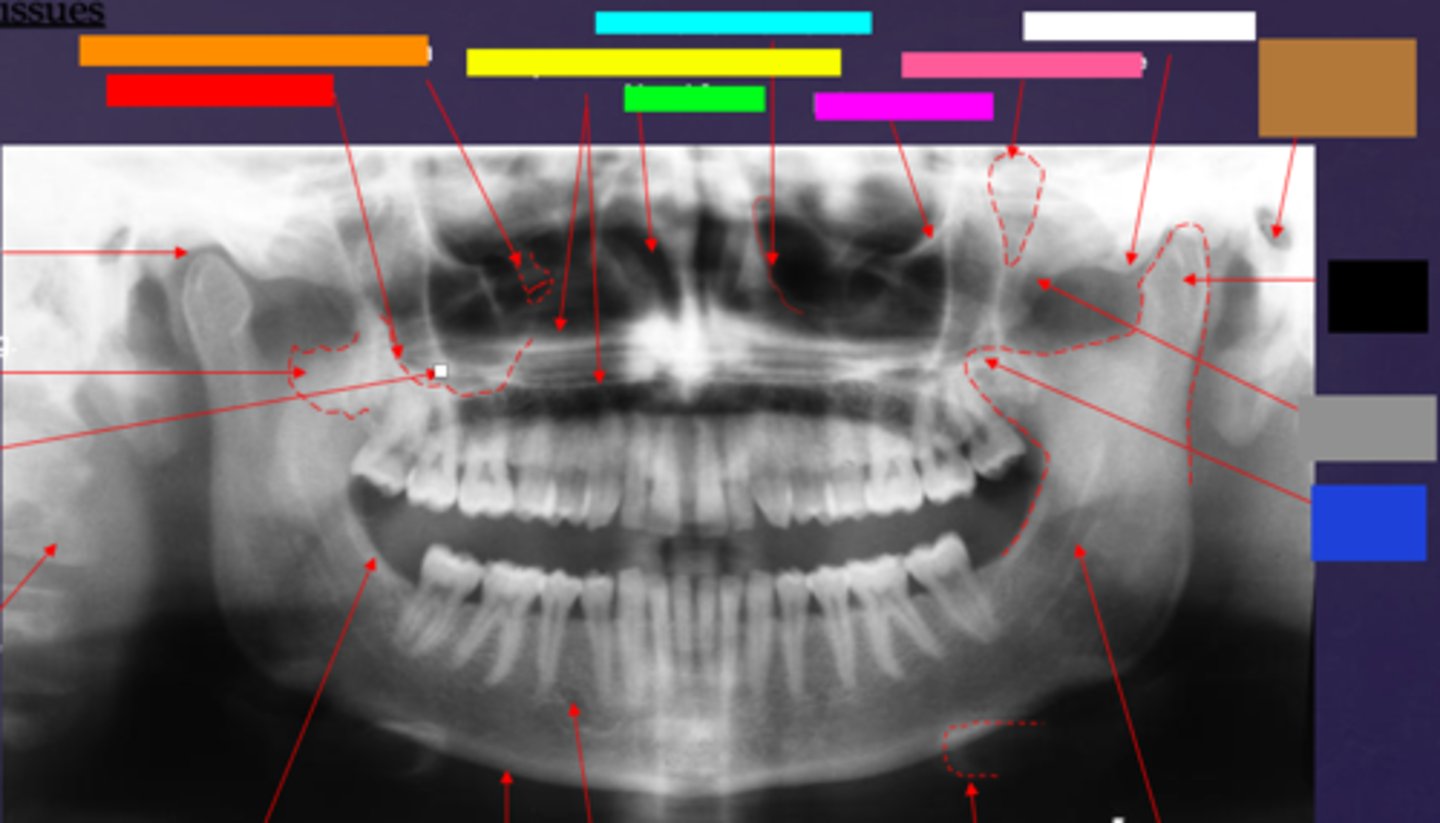

ID the soft tissue anatomy indicated by the arrow pointing from the red box:

posterior pharyngeal wall

ID the soft tissue anatomy indicated by the arrow pointing from the orange box:

soft palate

ID the soft tissue anatomy indicated by the arrow pointing from the yellow box:

dorsal surface of tongue

ID the soft tissue anatomy indicated by the arrow pointing from the green box:

middle nasal meatus

ID the soft tissue anatomy indicated by the arrow pointing from the light blue box:

inferior nasal meatus

ID the soft tissue anatomy indicated by the arrow pointing from the hot pink box:

inferior nasal concha (turbinate)

ID the soft tissue anatomy indicated by the arrow pointing from the brown box:

upper lip

ID the soft tissue anatomy indicated by the arrow pointing from the white box:

lower lip

ID the soft tissue anatomy indicated by the arrow pointing from the grey box:

ghost image of opposite mandible